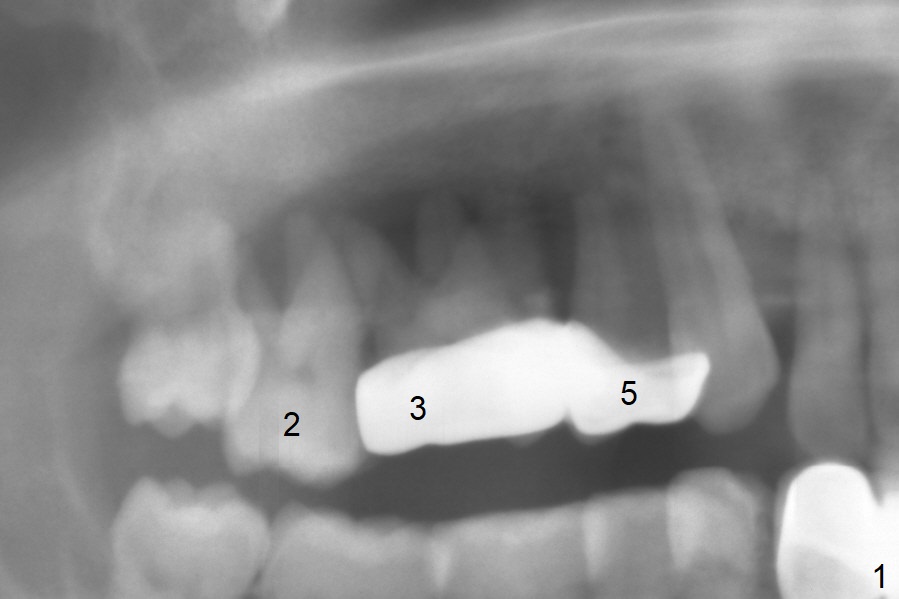

A 45-year-old man will return for #2, 3 and 5 extraction and implants (Fig.1,2). Take PAs for and Reline #7,9,11 provisional crowns and fabricate #11-13 temporary FPD if #15 implant is still unstable (5 months postop). Establish normal occlusal contact.

Extract #2 or remove #3-5 FPD first whichever is looser. Use the other as reference guide. Place Osteogen plug in the palatal socket of #2 ad 3 (Fig.3,4 yellow box) and allograft around the implants (red circles).